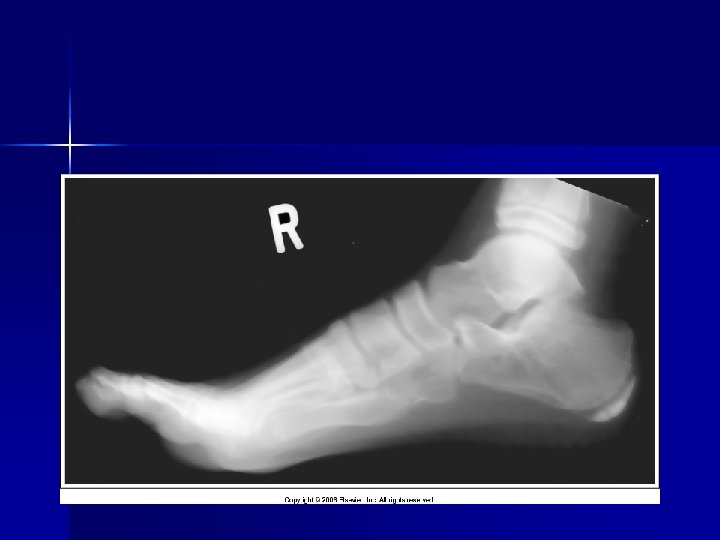

Evaluating Images What do you think?

n n n Does this show good detail? Is all of the anatomy present? How is the density / contrast?